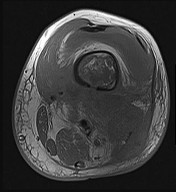

Figures 6a through 6d are the radiographs and T1-weighted sagittal and fat-saturated axial MR images of an otherwise healthy 56-year-old man who has anterior knee pain and intermittent swelling after sustaining a noncontact twisting injury. Low-power and high-power hematoxylin and eosin stained histologic specimens are shown in Figures 6e and 6f. Based on the history, radiographs, CT scan, MR imaging, and histologic findings, what is the most likely diagnosis?

The lesion in the posterior intercondylar knee notch is a benign synovial hemangioma. Intralesional calcifications, classically associated with hemangiomas, are frequently not identified on plain radiographs. The MR imaging reveals a hypervascular lesion with multiple filling defects, with hyperintensity on T2-weighted images and low-to-intermediate signal intensity on T1-weighted images. Histologically, vascular lakes within fine capillaries with a synovium on the surface of the lesion are characteristic of this condition. Many patients with synovial hemangioma have pain, swelling, stiffness, or mechanical symptoms. The correlation of symptoms with the hemangioma for this patient is unclear because there was recent trauma and a concurrent meniscus tear. Simultaneous treatment of both potential sources of pain is typically recommended. As with PVNS, the disease can be localized or diffuse. Surgical excision, either open or arthroscopic, is the recommended treatment. PVNS is the most common intra-articular tumor, but hypointensity in either the diffuse or localized type is characteristic in both T1- and T2-weighted images. Synovial sarcoma, although often found close to a joint, is not characteristically found within a joint.